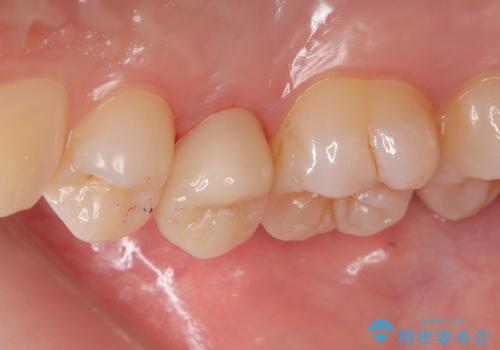

右上5番目の歯が根管治療途中となっており、前医院にて根管が狭く治療が難しいと言われてしまいセカンドオピニオンで当院にいらっしゃいました。

精密根管治療を行うこととしました。

右上5番レントゲン写真上では根管が確認しずらく、根管の狭窄が予想されました。マイクロスコープを使用し、根尖部まで器具を到達させ十分根管洗浄を行うことができました。

・オールセラミッククラウン(スタンダード) 110,000円(税抜き)